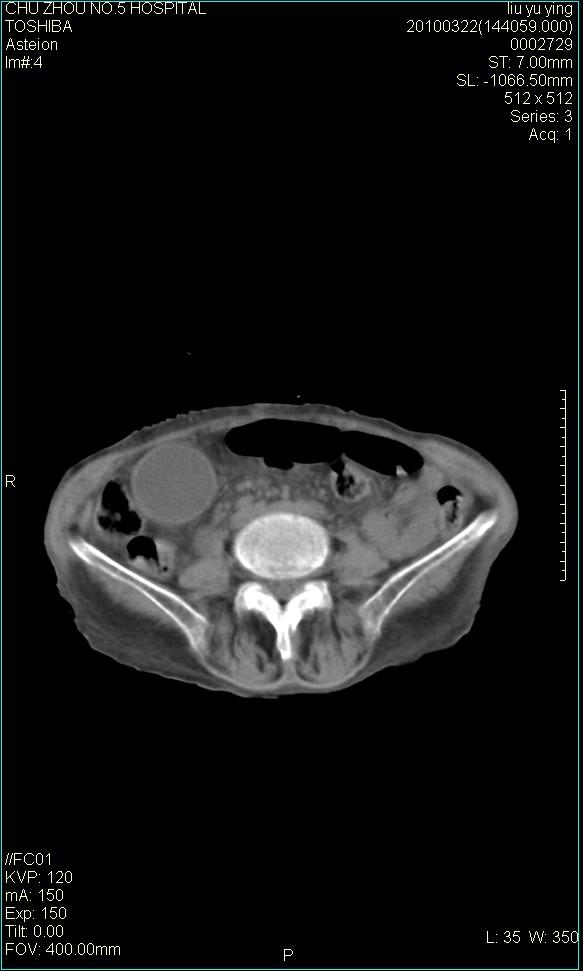

以下是引用科室第一人在2010-3-23 6:50:00的发言:[br]胆总管下段梗阻,多为肿瘤性病变,巨形胆囊,胆囊炎胆囊窝积液。[br]双侧胸腔积液,右降

以下是引用随光逐影在2010-3-23 8:12:00的发言:[br]1)胆系低位梗阻(肝内外胆管扩张,胆囊增大),原因待查。2)胆囊炎。3)双侧少量胸腔积液。4)降主动脉迂曲。